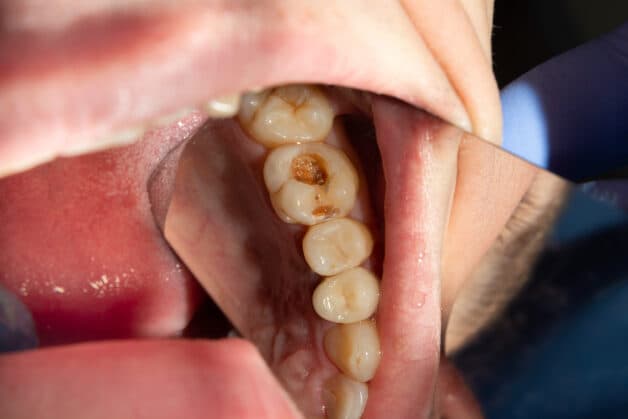

– Điều trị các bệnh lý răng miệng không dứt điểm: Trước khi bọc sứ, những trường hợp có các bệnh lý răng miệng như sâu răng, viêm nướu, viêm nha chu,… cần được điều trị dứt điểm. Nếu không, bên dưới mão sứ, các bệnh lý răng miệng đó sẽ tiếp tục phát triển, làm răng và xương ổ răng hoại tử, gây đau đớn dữ dội cho bệnh nhân.

Trước khi bọc sứ, những trường hợp có sâu răng, viêm nướu,… cần được điều trị dứt điểm.